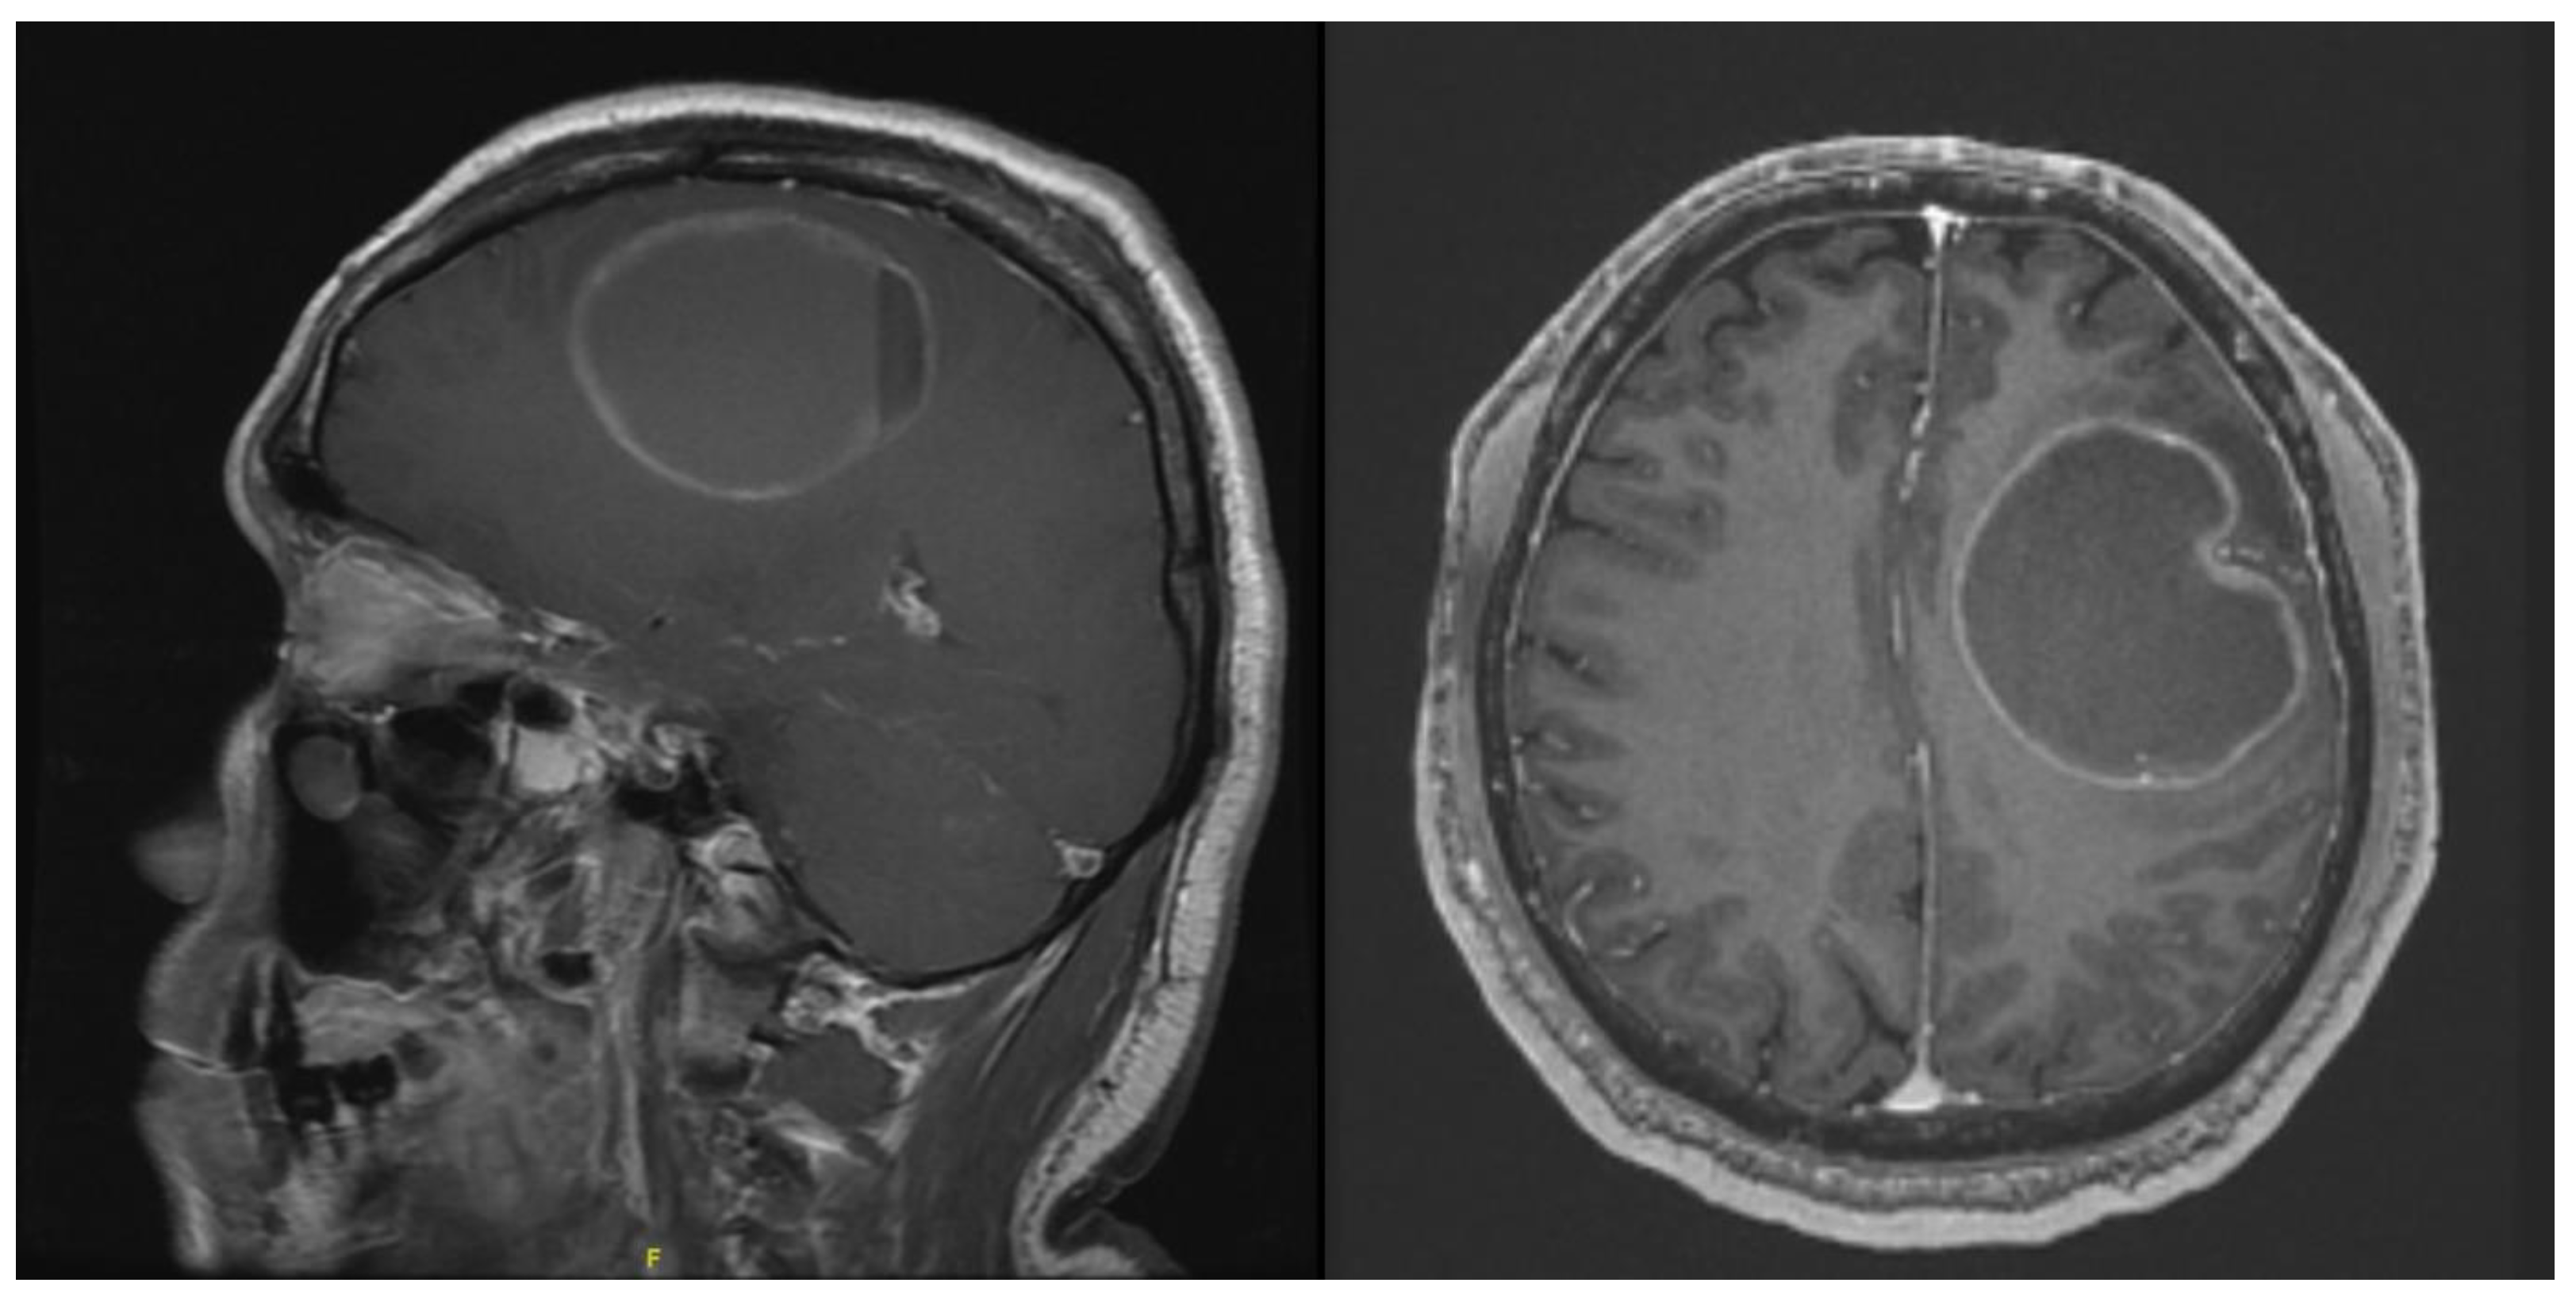

The next patient was a 57-year-old male presenting with right-sided weakness and short-term memory loss. On examination, he was noted to have grade 4/5 on the right upper and lower right limb. MRI brain with contrast showed a 6.6 × 5.2 × 5.1 cm intra-axial tumour in the left fronto-parietal region (Figure 7). Diffusion imaging tractography (DTI) was also performed on this patient.

Figure 7. Contrasted T1 MRI showing the intra-axial cystic tumour.